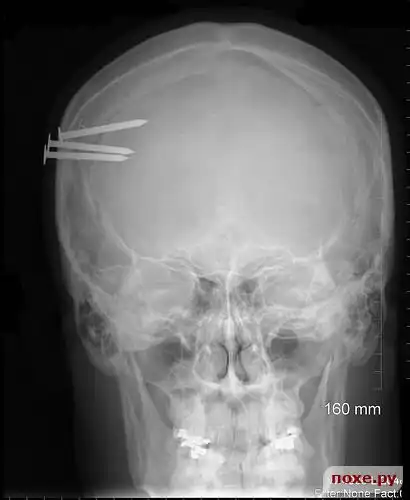

Гвозди в голове.